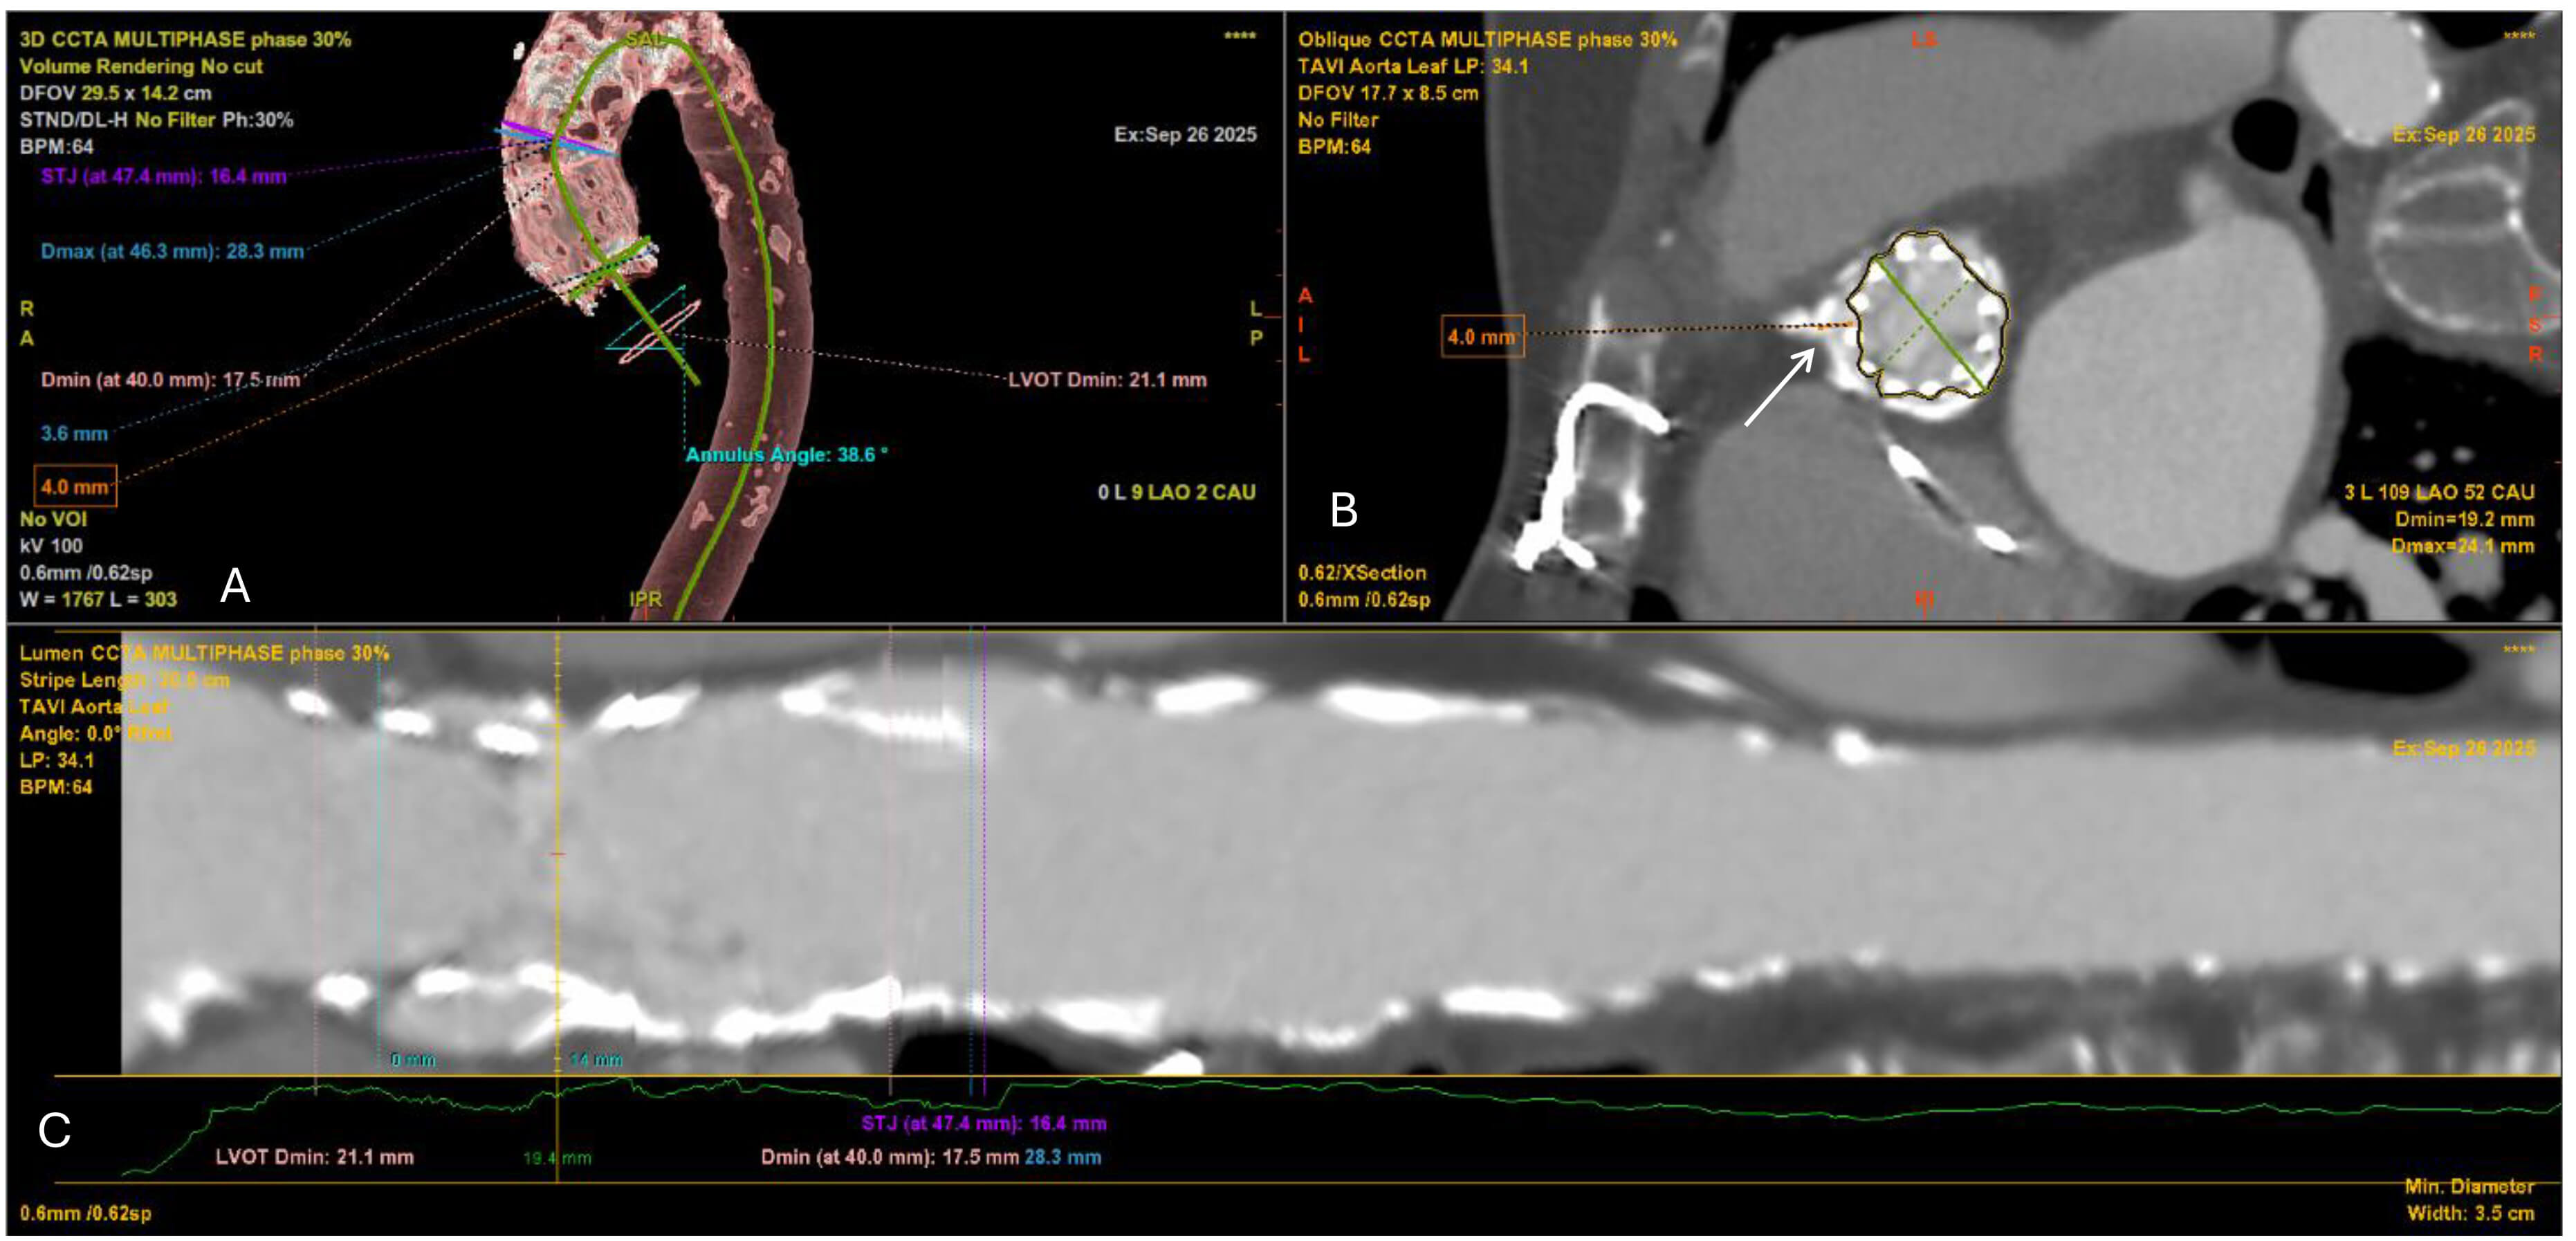

Valve in Valve (ViV) TAVI is considered as a valid therapeutic option in

patients with degenerated bioprosthetic surgical heart valves (SHVs) [59, 60], or

previous TAVI, especially in patients with high operative risk [61]. Estimating

the risk of coronary artery occlusion, as well as knowing the surgical heart

valve type and size is crucial in ViV cases [62]. Pre-procedural CT is the gold

standard. The decisive parameter for a ViV procedure is the distance between the

ostia of the coronaries and the expected final THV position. Simulating a virtual

ring, which represents the expanded THV, aligned geometrically with the surgical

valve is performed using pre-interventional CT imaging analysis. The distance

between this virtual ring and the ostia of the coronary arteries, i.e., the VTC

(Virtual THV to coronary distance) as well as Valve to STJ (VTSTJ) distances are

essential parameters that need to be calculated to justify the feasibility of the

procedure (Fig. 5). Especially for the risk of coronary ostia occlusion 3 to 6mm

represents intermediate risk and

Fig. 5.

Multidetector CT angiography for preprocedural planning of valve-in-valve TAVI. (A) 3D volume-rendered reconstruction of the thoracic aorta and aortic root showing the previously implanted surgical aortic bioprosthesis (SAVR) in situ, the heavily calcified ascending aorta, and measurements of the aortic annulus, LVOT and STJ. The annular angulation relative to the long axis of the aorta is also depicted. (B) Oblique cross-sectional view at the level of the surgical bioprosthesis demonstrating the internal stent frame and leaflets. The white arrow indicates the virtual transcatheter valve-to-coronary (VTC) distance to the right coronary ostium (measured at 4.0 mm), which is critical for assessing the risk of coronary obstruction. (C) Curved multiplanar reconstruction (centerline analysis) of the aortic root and ascending aorta, illustrating luminal diameters along the LVOT, annulus, and STJ. Minimal and maximal diameters are annotated, confirming the constrained annular geometry imposed by the prior surgical valve.

The SHV type (stented, stentless, sutureless) and size (in cases of unclear surgical history) can be distinguished using CT analysis, as well as high-risk features for coronary occlusion during the procedure, such as bulky calcifications, pannus, failed prostheses, and leaflet presence [66]. Finally, providing a detailed anatomic view utilizing MPR is extremely helpful in pre-intervention planning. Of note, in patients with renal impairment, radiopaque parts of the surgical valve, as well as ostia of the coronaries can be identified without contrast [67].

Cardiac CT has become the gold standard imaging modality for post-TAVI evaluation. It allows precise assessment of prosthesis expansion, leaflet motion, paravalvular leaks, and coronary ostia patency. Importantly, CT can detect hypo-attenuated leaflet thickening (HALT), a manifestation of subclinical leaflet thrombosis that may not be apparent on echocardiography [68]. Careful multiplanar review is essential, as HALT may be missed if only a single imaging plane is evaluated (Fig. 6). Beyond HALT, CT also quantifies calcium burden, evaluates stent frame position, and helps in planning potential re-intervention. Thus, CT provides comprehensive structural and functional insights critical for long-term surveillance of TAVI patients.

Fig. 6.

Cardiac CT demonstrating hypo-attenuated leaflet thickening (HALT) after TAVI. (A) Short-axis view of the transcatheter valve (white arrows). (B) At the mid-leaflet level, HALT is visible in the non-coronary cusp (white arrow). (C) At a slightly different reconstruction plane, HALT is instead visualized in the left coronary cusp (white arrows). These findings highlight how leaflet thrombosis can involve different cusps and may only be appreciable at specific imaging planes.